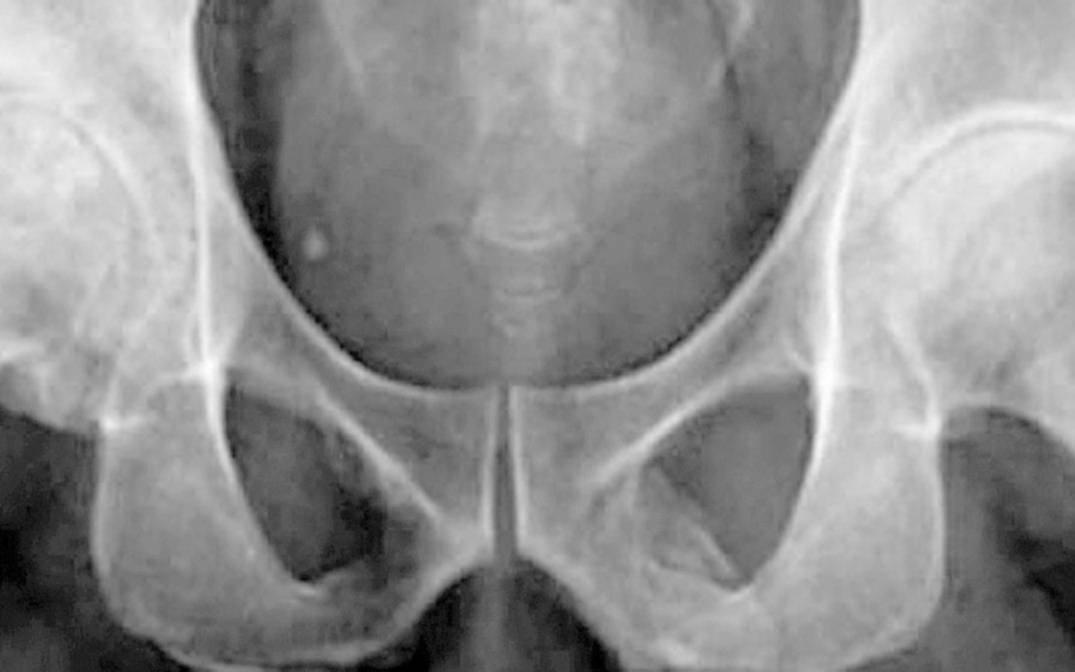

Un hombre de 63 años decidió ir al hospital después de haber recibido un golpe en su rodilla, pero jamás se imaginó lo que iban a decirle después de tomarle una radiografía.

Esta persona acudió a un centro de salud de Nueva York y allí los médicos le dijeron que su pene se estaba convirtiendo en hueso.

Según un informe médico publicado en la revista Urology Case Reports, el paciente ingresó al hospital con un fuerte dolor en su rodilla, pero después del examen de rayos X le dijeron que sufría una osificación del pene.

Cuando los médicos le revelaron esta extraña condición médica, él afirmó sentir molestias en su miembro, aunque no tenía otros síntomas que delataran problemas urológicos.

En las imágenes se mostraba una extensa calcificación de los tejidos blandos que forman el pene. Esto ocurre cuando se depositan sales de calcio en los tejidos blandos del órgano, provocando la aparición de placas de hueso donde no debería haberlas. El caso es muy curioso y hay sólo 40 registros a nivel mundial.